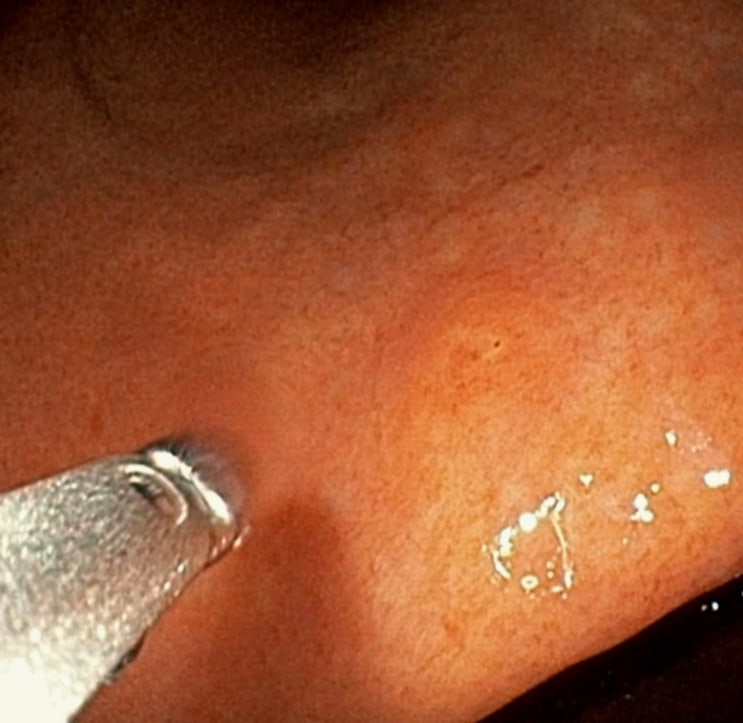

미란성 위염은 내시경상 드물지 않게 발견되는 병변이지만, 보통 다발성으로 존재합니다. 본 케이스와 같이 단독으로 한 병변에서만 존재한다면, 다른 질환 감별을 위해 추가 조직검사를 고려하게 됩니다.

조직검사 결과 위염(단독 융기된 미란성위염)에서 미분화 세포암이 확인되었습니다. 추가 치료를 위해 상급병원으로 전원하였습니다.

한마디: 증상이 없어도 정기적인 위내시경을 통해 조기 위암을 발견할 수 있습니다.